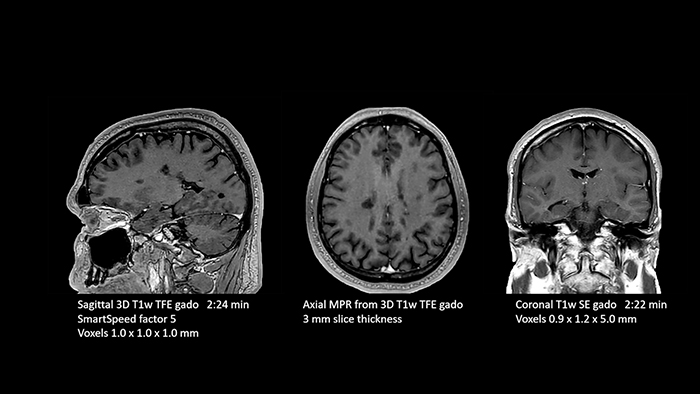

Dr. Schröter also highlights their step forward in MRI of the prostate. “In prostate exams we have saved almost 50 percent of time. We used to need about 35 minutes for an MRI exam of the prostate and now we can do it in just 18 minutes with a significantly higher resolution and higher image quality.”

Dr. Schröter points out that a more confident diagnosis requires high-quality images with more diagnostic information. “Philips SmartSpeed provided that to us. AI denoises the clinical images without losing any important data, resulting in high-resolution images. It keeps all the information we need and makes the images better.

We can apply SmartSpeed to almost all sequences. That is a big step forward! We use it for example in 3D imaging and in diffusion-weighted imaging, to dramatically reduce scan time or increase image resolution, which is quite useful.

There are small lesions that we would certainly have seen without SmartSpeed, however it would have taken us longer to properly diagnose. In 3D MSK images with extremely high resolution, we uncover the finest anatomical structures and can thus report very detailed findings.”

Powerful GPU rapidly provides images and reconstruction on large screen

Another important part of MR Workspace is the graphics processing unit (GPU), which allows on-the-fly reconstruction times for images acquired with SmartSpeed. “In addition to seeing razor-sharp images on the large 4K monitor, we also have better and faster reconstruction of the images. Using this extremely high resolution, we sometimes have sequences with up to 800 individual images. The GPU then manages to convert them in a matter of seconds into multiplanar reconstructions. Very impressive.”